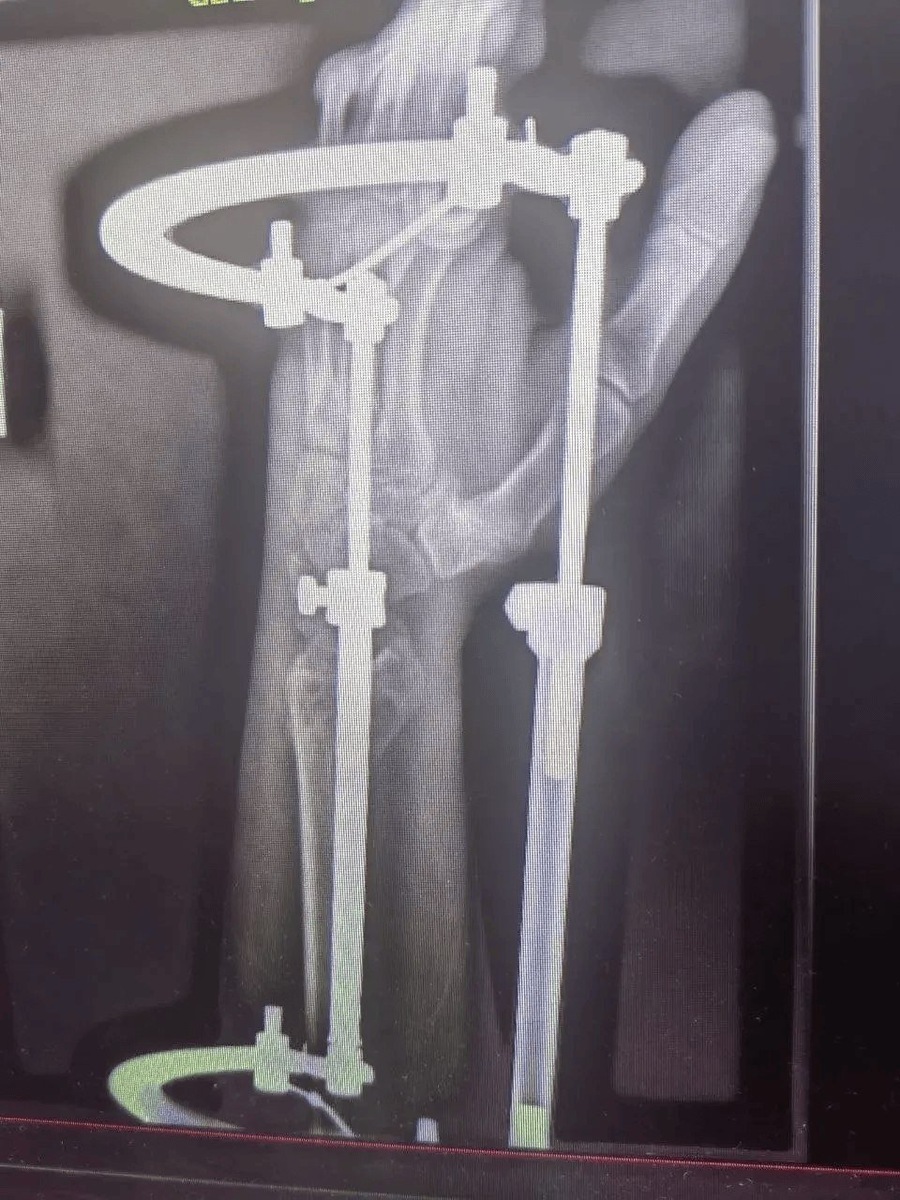

Ставропольские врачи спасли мужчину, упавшего с 6-метровой высоты. Пострадавшего доставили в городскую клиническую больницу скорой медицинской помощи с тяжёлой политравмой, сообщает пресс-служба минздрава Ставрополья. Мужчина 1972 года рождения получил множественные переломы и другие серьёзные травмы. Его лечением занималась команда специалистов разных профилей. Челюстно-лицевые хирурги провели шинирование, травматологи-ортопеды выполнили операцию на правой локтевой кости и восстановили левую лучевую. Также пациент проходил лечение у нейрохирургов и неврологов. "Течение посттравматического периода осложнилось токсическим гепатитом, но грамотная работа терапевта позволила справиться и с этим вызовом", — рассказали в минздраве региона. Благодаря слаженной работе врачей состояние мужчины стабилизировали. Его выписали, дальнейшее лечение он проходит амбулаторно под наблюдением специалистов.

Ставропольские врачи спасли мужчину, упавшего с 6-метровой высоты. Пострадавшего доставили в городскую клиническую больницу скорой медицинской помощи с тяжёлой политравмой, сообщает пресс-служба минздрава Ставрополья.

Мужчина 1972 года рождения получил множественные переломы и другие серьёзные травмы. Его лечением занималась команда специалистов разных профилей. Челюстно-лицевые хирурги провели шинирование, травматологи-ортопеды выполнили операцию на правой локтевой кости и восстановили левую лучевую. Также пациент проходил лечение у нейрохирургов и неврологов.